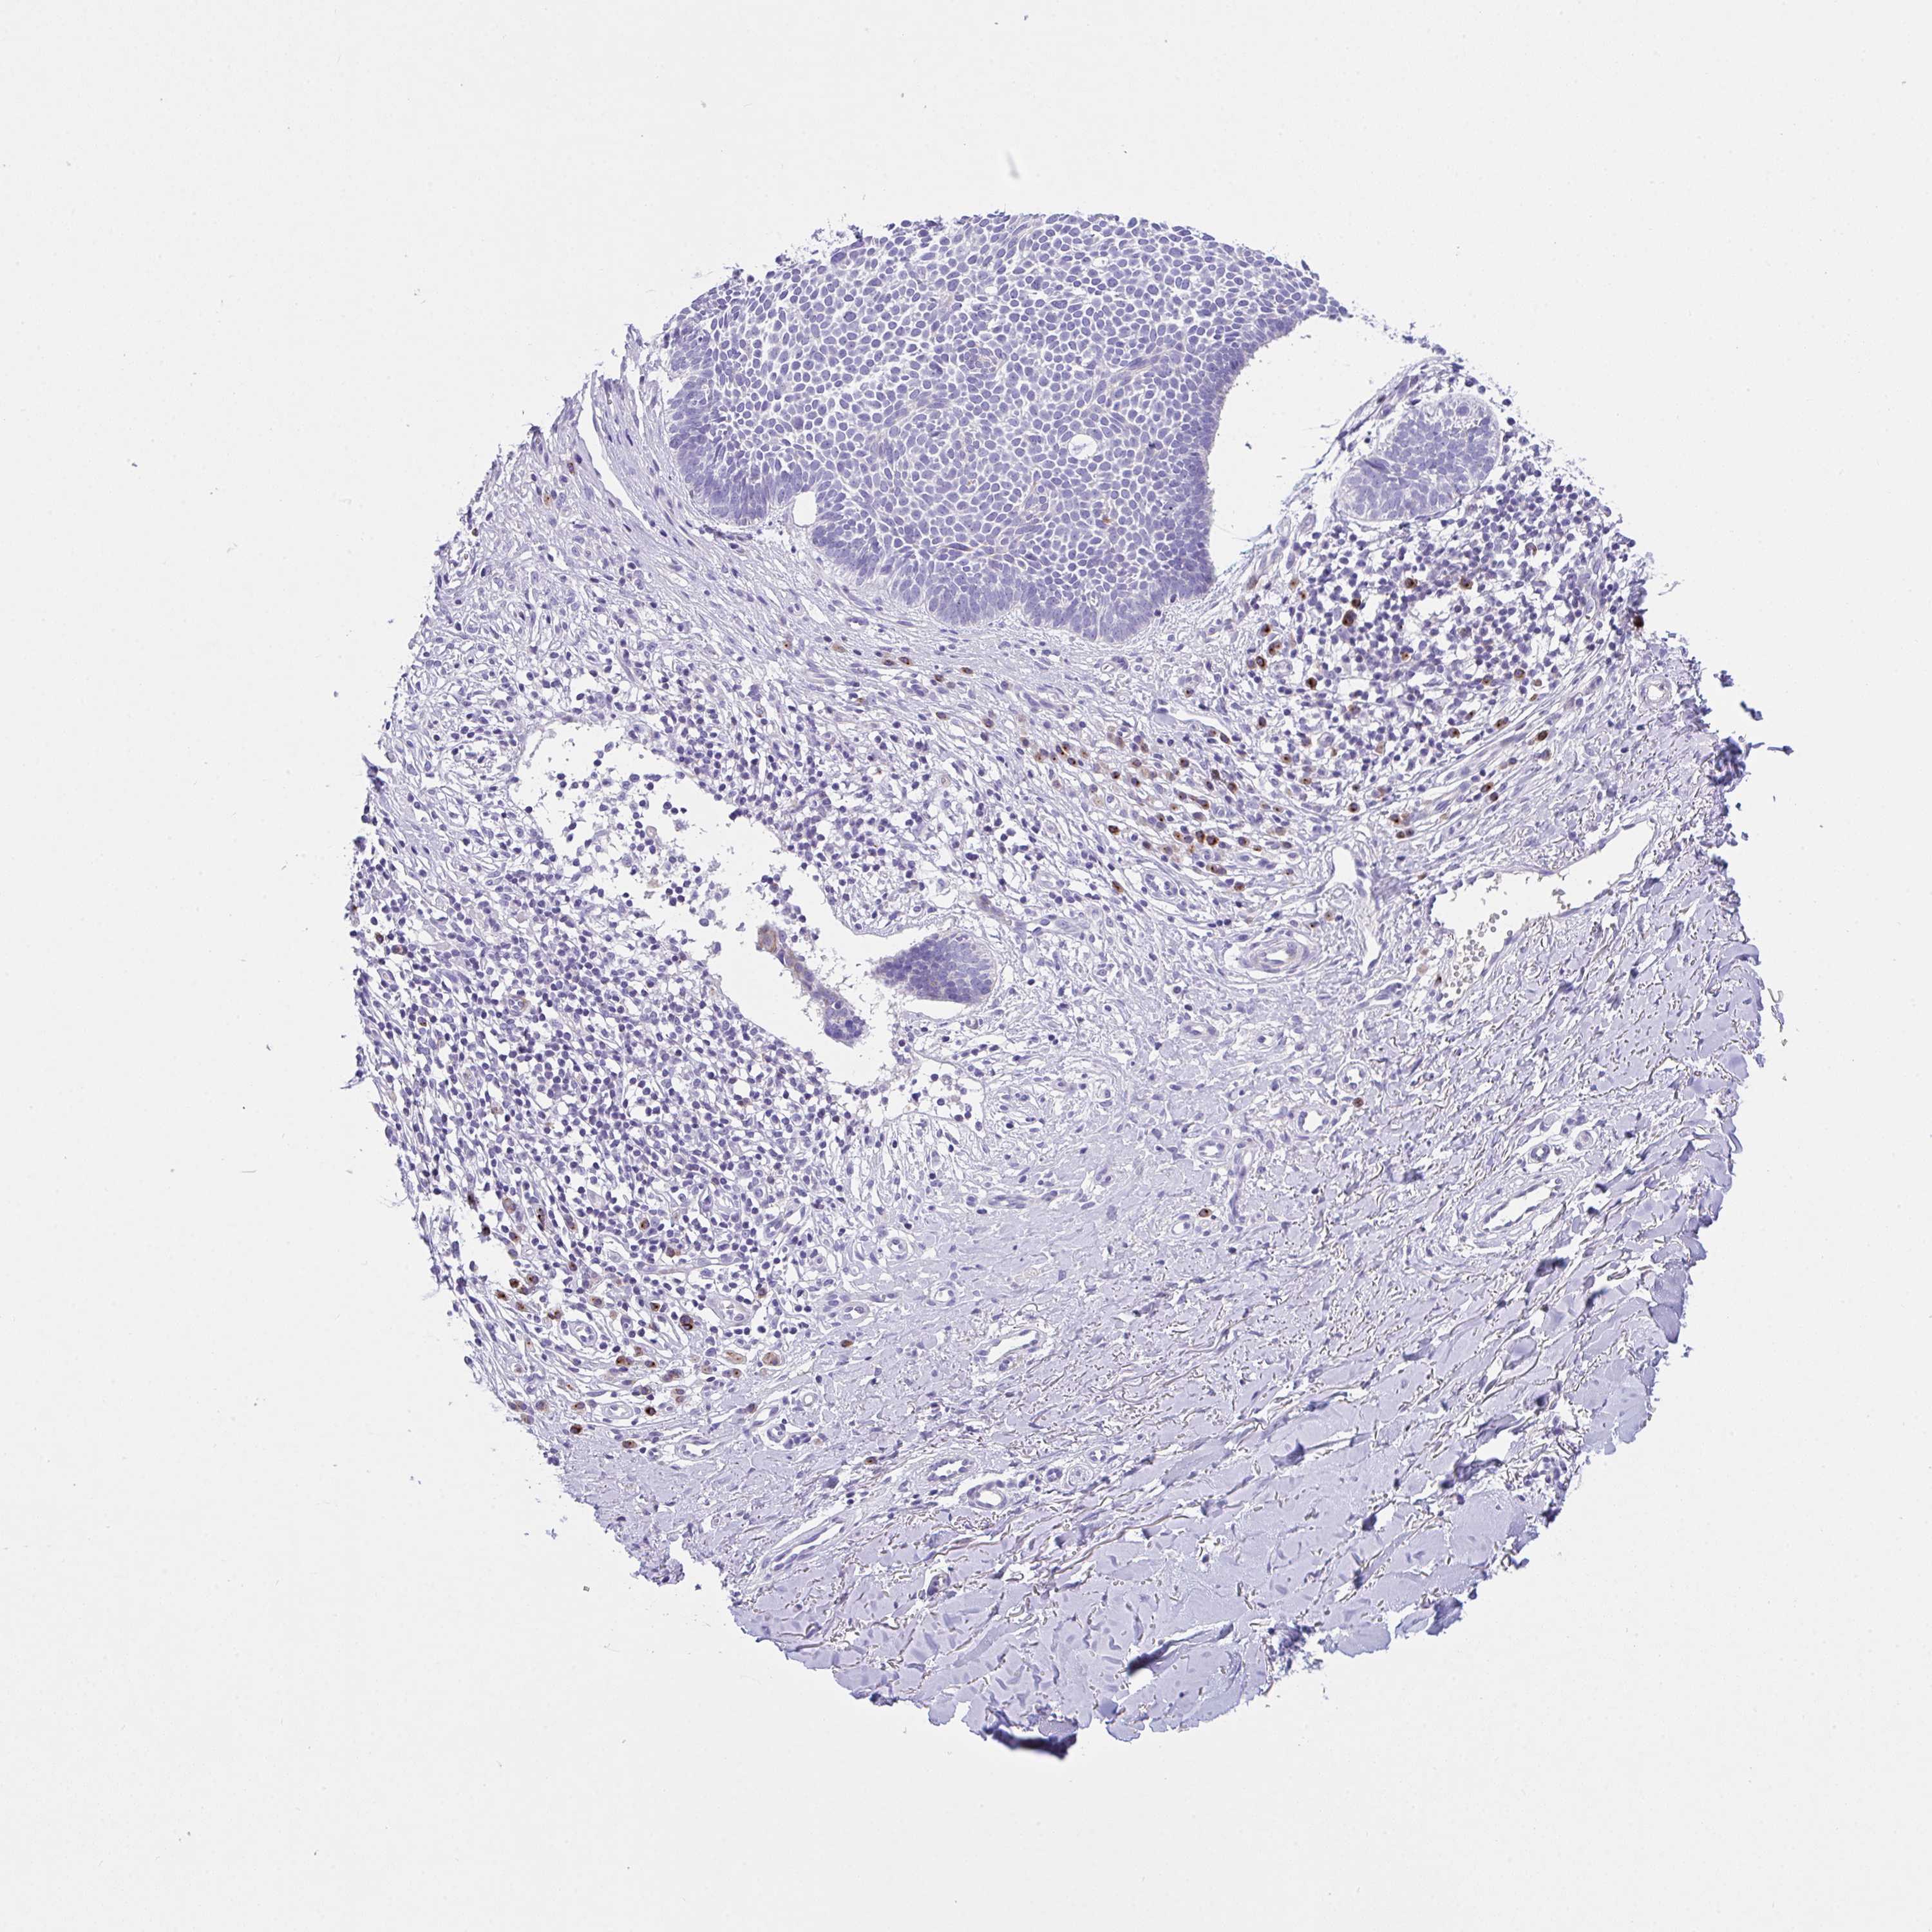

SKIN CANCER - Protein expressioni

A mouse-over function shows sample information and annotation data. Click on an image to view it in a full screen mode. Samples can be filtered based on level of antibody staining by selecting one or several of the following categories: high, medium, low and not detected. The assay and annotation is described here.

Antibody staining in the annotated cell types in the current human tissue is reported as not detected, low, medium, or high, based on conventional immunohistochemistry profiling in selected tissues. This score is based on the combination of the staining intensity and fraction of stained cells.

Each image is clickable and will lead to virtual microscopy that enables deeper exploration of all samples and also displays staining intensity scores, fraction scores and subcellular localization as well as patient and tissue information for each sample.

Antibody HPA044748

Staining

Intensity

Strong

Moderate

Weak

Negative

Quantity

>75%

75%-25%

<25%

None

Location

Nuclear

Cytoplasmic/membranous

Cytoplasmic/membranous,nuclear

Basal cell carcinoma